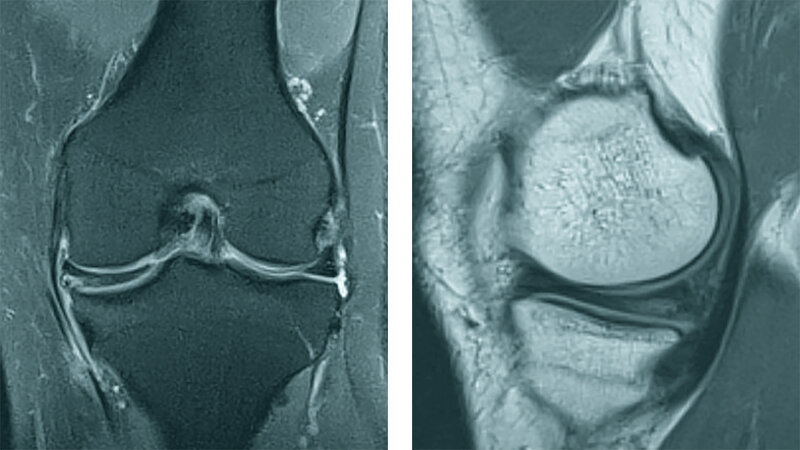

Der Scheibenmeniskus ist eine abnorme Meniskusvariation. Die klinische Symptomatik ist variabel und kann asymptomatisch sein, knirschend oder blockierend sowie Schmerzen und Schwellung verursachen. Die partielle Meniskektomie mit Schonung der stabilen peripheren Region in Kombination mit oder ohne peripherer Reparatur verspricht gute kurz-, mittel- und langfristige Ergebnisse.

Discoid meniscus is a common abnormal meniscus variant. The clinical presentation varies from being asymptomatic to snapping, locking, and causing severe pain and swelling of the knee. Partial meniscectomy with preservation of a stable peripheral rim combined with or without peripheral repair is effective, and good short-, mid- and long-term clinical results have been reported.